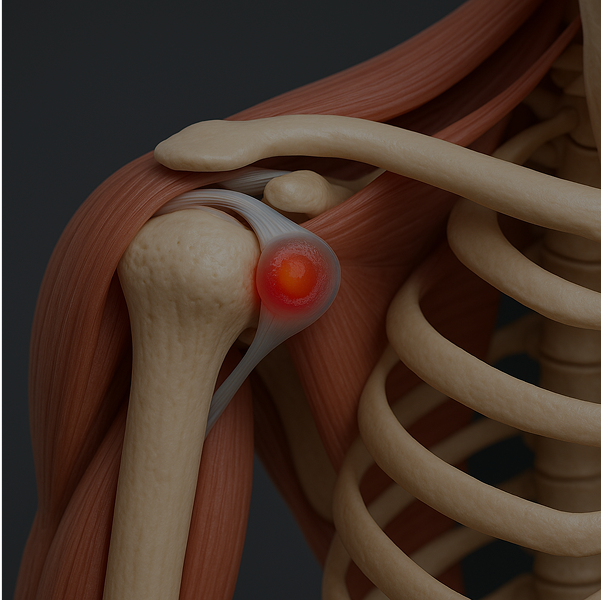

The shoulder is a complex joint made up of various structures that can become injured or inflamed.

Common causes of shoulder pain include

or tears

or adhesive capsulitis

Identifying the root cause of your shoulder pain is essential.